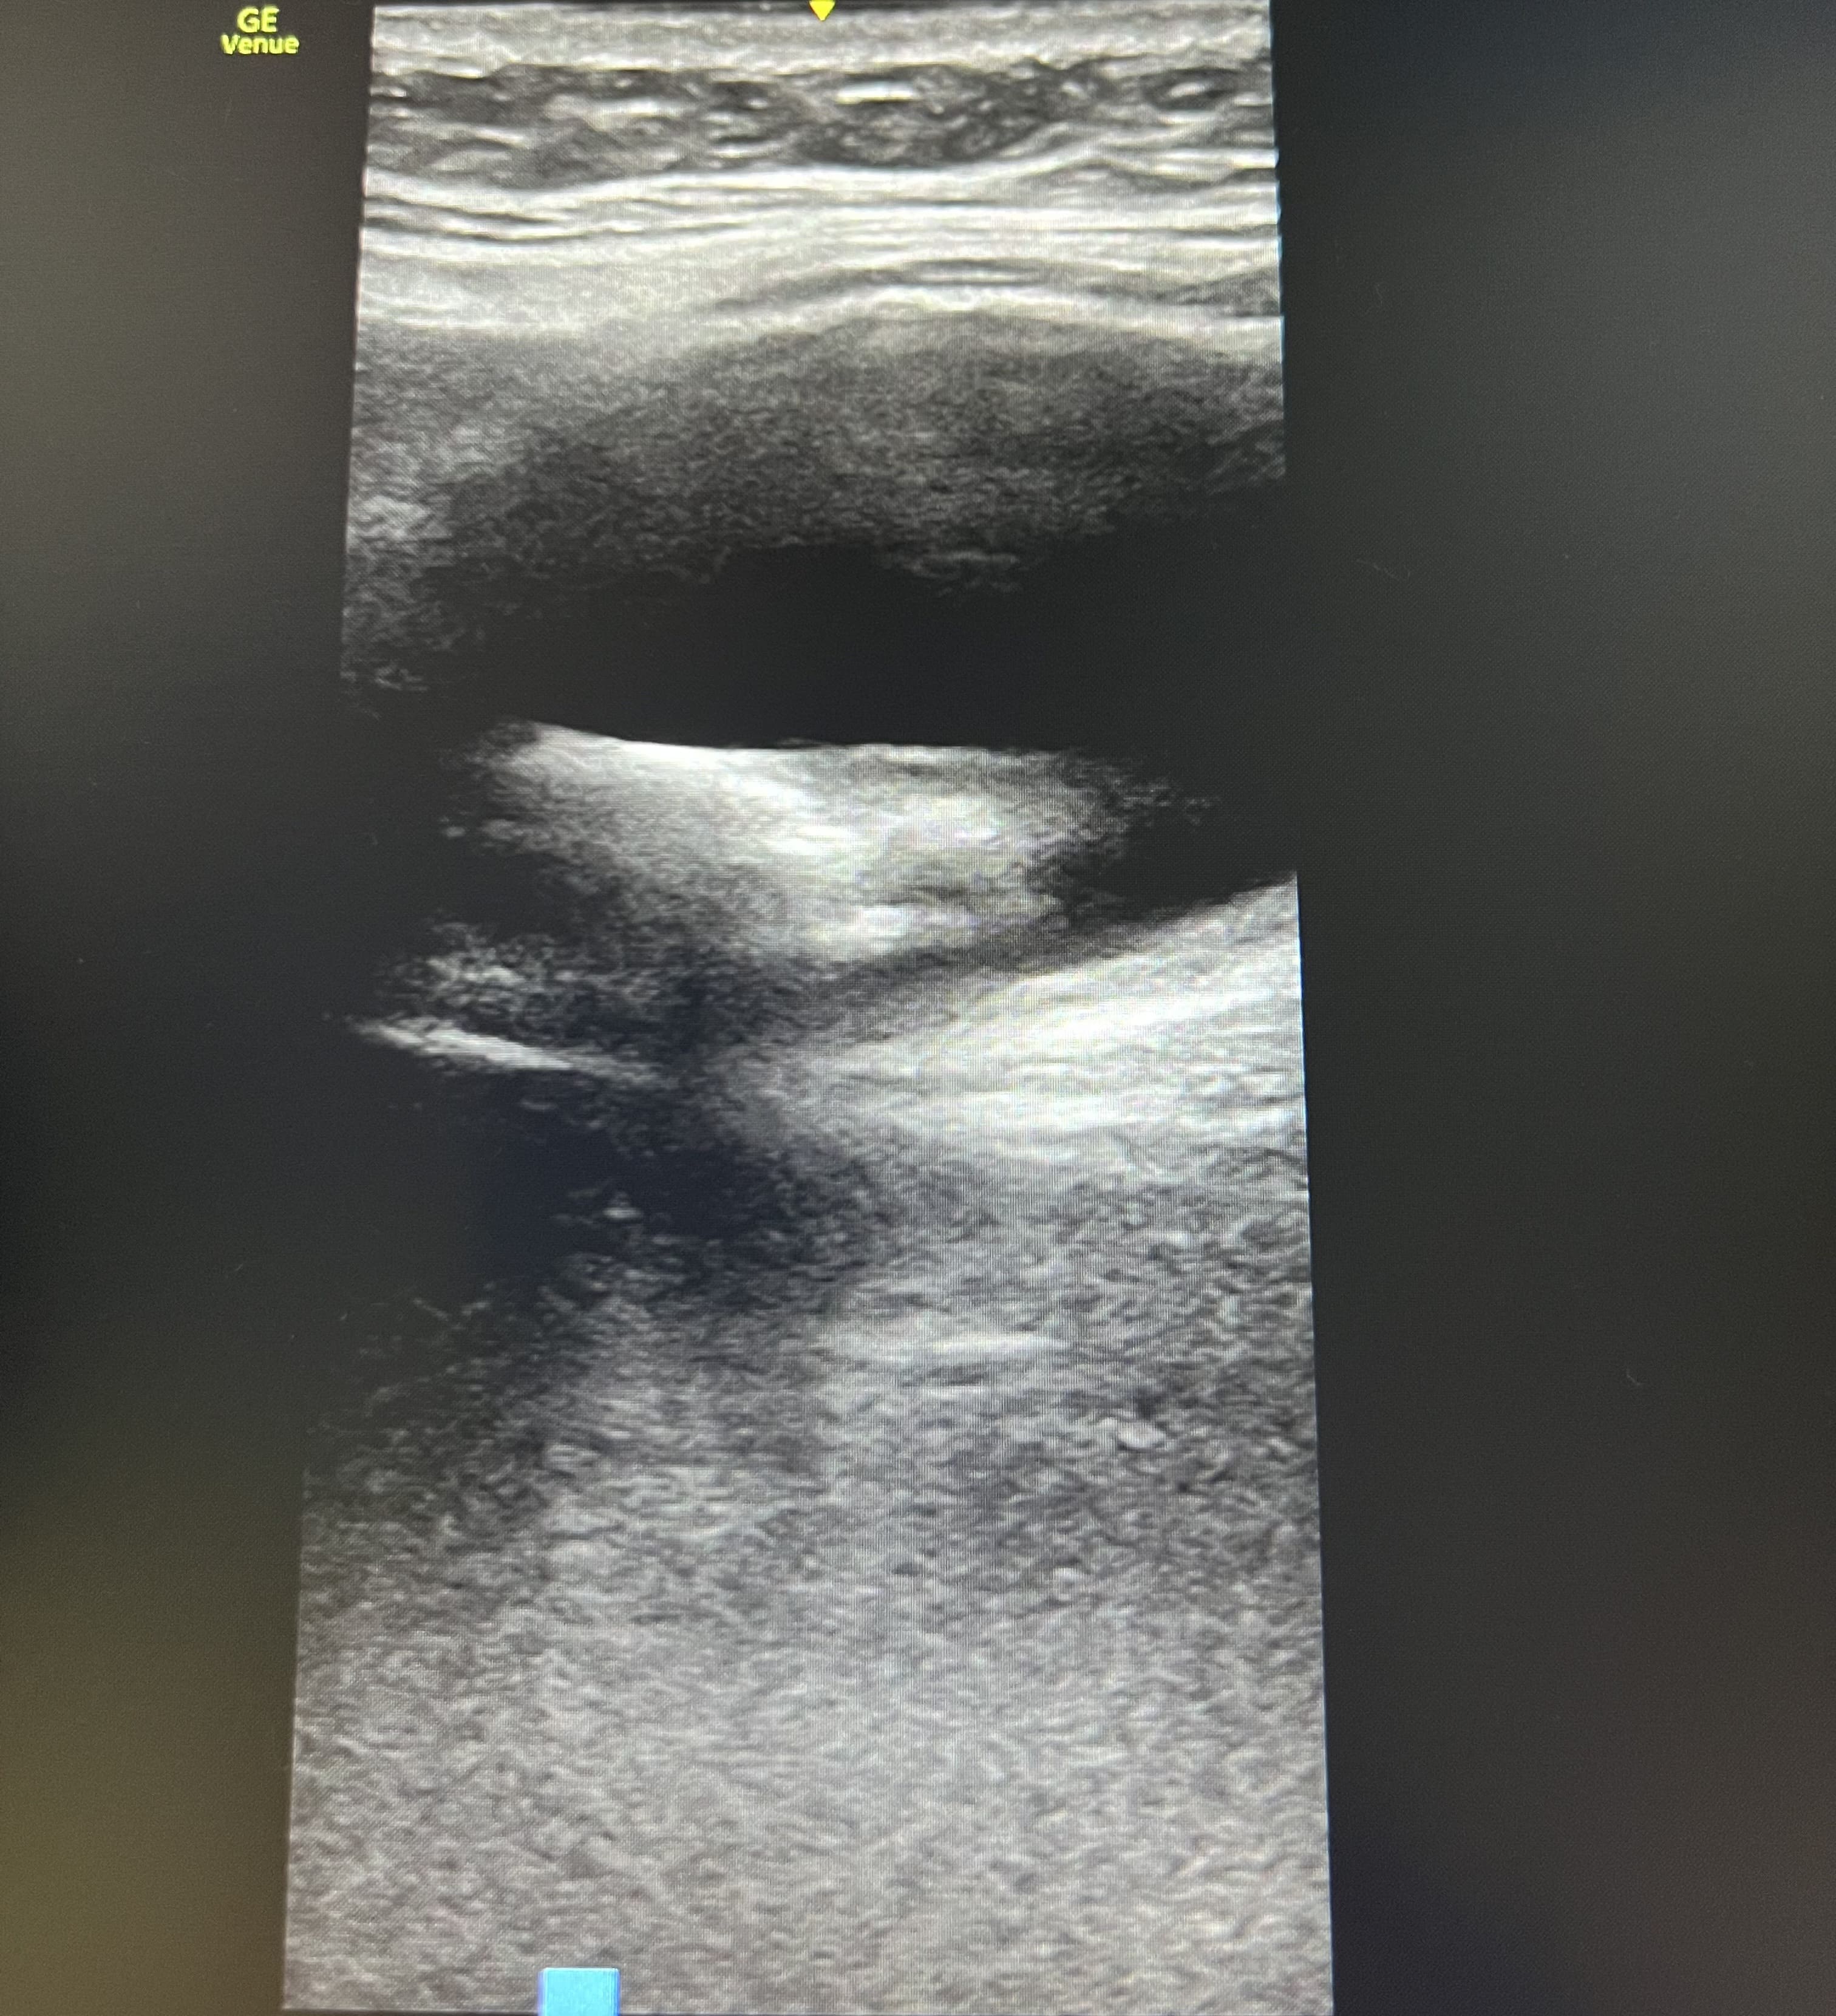

Pruebas complementarias: Ecografía abdominal con sonda convexa: vesícula biliar distendida con litiasis de 4 centímetros en su interior y sombra acústica posterior. Ecografía con sonda lineal en flanco derecho: lesión anecoica ovalada con imagen hiperecoica en su interior, que no captan Doppler, y movilizan con la respiración, en tejido subcutáneo.